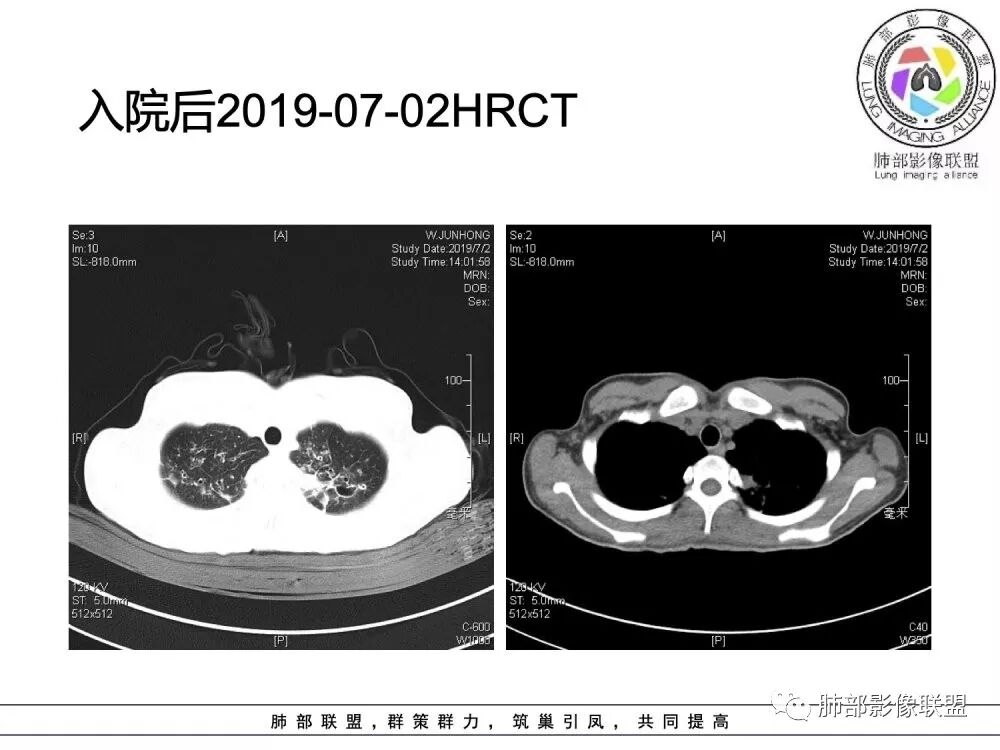

患者青少年女性,以反复咳嗽、咳痰10余年,痰血3年,再发1月余。患者自幼咳嗽、咳痰史,黄白脓痰,曾诊断支气管扩张症,常感乏力,时有腹痛感。有食物药物过敏史。胸CT:病变以双上肺为主,支气管明显扩张,支气管壁可见增厚,可见双轨征,右上肺后段可见囊状改变,并可见片状实变影。诊断考虑:囊性纤维化?鉴别:1 ABPA?2 结核后支气管扩张?

年轻女性,15岁,自幼咳嗽咳痰10余年,痰血三年。两肺呈支扩改变伴小片渗出,双肺上叶为主 。左下见指套状密度偏高影考虑粘液栓,右上部分局限性实变,从病史基本推出诊断,考虑CF。

水晶石头:

病变以双上肺为主,支气管明显扩张,支气管壁可见增厚,可见双轨征 右上肺后段可见囊状改变,并可见片状实变影。患者青少年女性,以反复咳嗽 咳痰10余年,痰血3年,患者自幼咳嗽 咳痰史,黄白脓痰,曾诊断支气管扩张症,考虑:囊性纤维化?

患者15岁,女性,反复咳嗽、咳痰10余年,痰血3年,再发1月余。有腹痛、食物药物过敏史。胸CT:病变双上肺为主,支气管明显扩张,支气管壁可见增厚,双轨征 ,部分可见囊状改变及片状实变影。诊断考虑:CF?鉴别:ABPA;纤毛运动障碍综合征;DBP等

(1)支气管壁增厚、支气管扩张

可广泛分布于两肺各叶,尤其是两肺上叶多见。支气管扩张主要是轻、中度柱状支气管扩张。支气管壁增厚既可发生于扩张的支气管,也可发生于非扩张的支气管,常为轻度增厚,管壁内外比较光滑。

(2)两肺弥漫性肺气肿

表现为肺野密度低而不均,在不同病例病变程度轻重不一,婴儿或儿童患者多见。